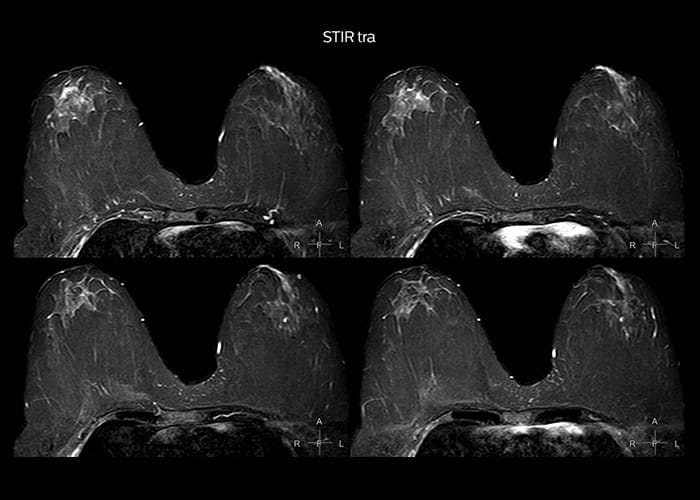

“To avoid coil changes we plan examinations of similar anatomies back to back, such as head and spine. Multiva helps us here a lot because coils don’t need to be changed frequently. Moreover, thanks to parallel imaging technology and 16-channel HeadSpineTorso and 8-channel MSK coils we are able to achieve excellent image quality. In this way Multiva helped us to increase both image quality and productivity.”

“Neurological cases, such as brain and spine imaging, represent the largest share in our MR scanning, followed by musculoskeletal cases. In general, we use simple and basic imaging protocols. But occasionally, we use advanced techniques for problematic cases if necessary.